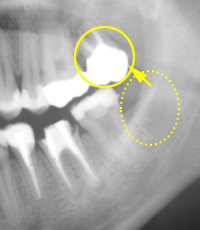

根の先の病気

主に虫歯が原因で、細菌が歯の中に通っている神経の管を通って神経自体に炎症を起こしたり、根の先に膿を作ることがあります。

感染してしまった部分をきれいにとり、清掃をして、きれいになったところで細菌が増えないように薬をつめます。

根の治療例(保険適応)

歯根端切除術

歯の根の治療だけでは治癒に期待が持てない場合には、すぐに抜歯はせずに、歯肉をあけて根の先の膿を持った部位にアプローチする、

歯根端切除術というものがあります。